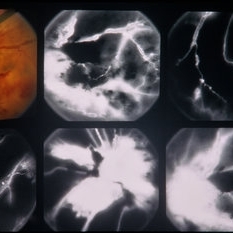

PDR

Jan 24 2014 by Howard Schatz, MD

62-year-old female. Right eye 20/25 and left eye 20/50.